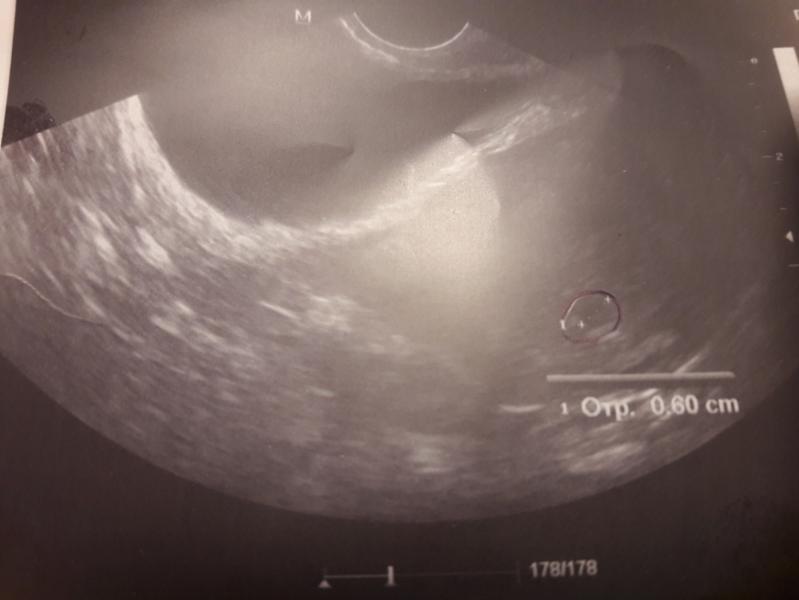

Всем привет! Сегодня сходила на УЗИ (5 акушерская неделя и 2 дня). Беременность маточная, все в норме. Но вот вопрос: может ли Узист ошибаться: там этих "пятнышек" на аппарате много)) Она мне показывает экран, тыкает пальцем, а я не вижу)) Могла ли она ошибочно определить плодное яйцо?

Определяет не узист а аппарат помоему. У меня нашли б в сроке 2 нед. Это точка от ручки. Реально

Я на своем узи видела мешочек, был очевиден, а вот эмбриончик спрятался, долго найти не могла она, решила прослушать сердечко...бьется, значит есть, живой. А потом включила(Не помню как назвала) такую функцию, на экране появились цветные пятна, по центру было желтое пульсирующее пятно, это и было сердечко) так мы его и обнаружили